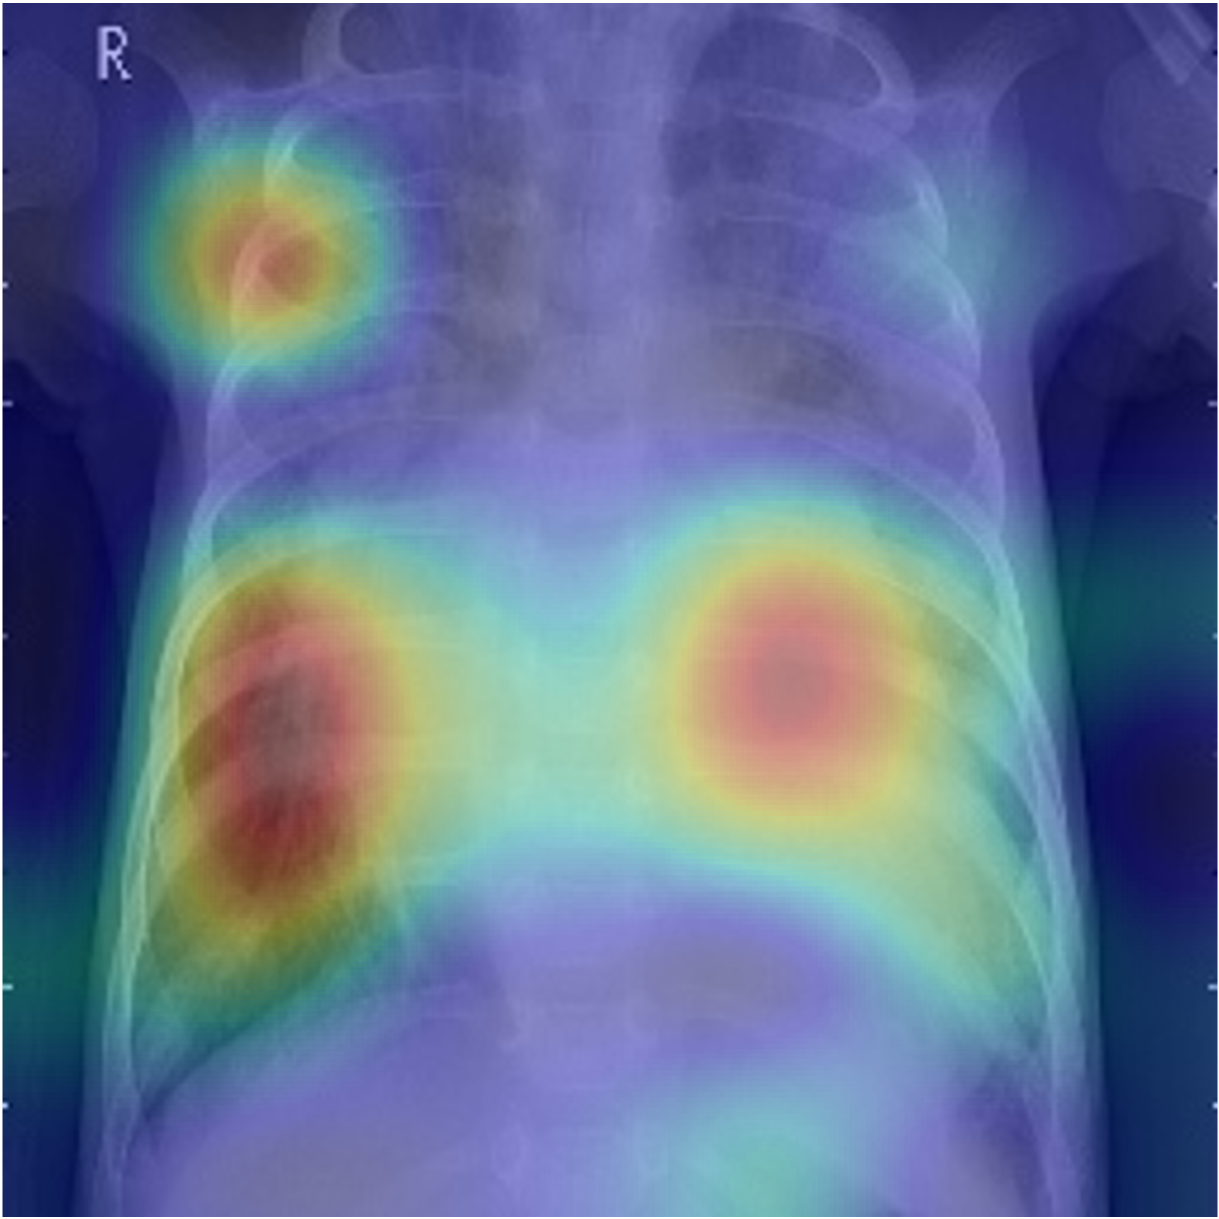

3.3.1 Visualization of position-guided impact.

The impact of position guidance is visualized through the Class Activation Mapping (CAM) in Fig. 3. In the first row, the entire lung view fails to detect anomalies in the left region. However, specific views focused on the left, upper, and lower sections of the lung successfully identify these anomalies. In the second row, the left lung view detects anomalies that are missed in the entire lung view. These outcomes indicate the importance of utilizing diverse position prompts.